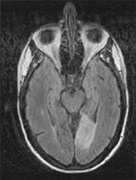

Fig. 15. Bilateral incomplete hemianopia. A 69-year-old man with decreased vision after prostate surgery. A. Fields show remaining central parafoveal vision with some sparing of inferior left quadrant. Note how the defect respects the vertical meridian. B. MRI shows bilateral medial occipital infarction, with sparing of the occipital poles, accounting for the macular-sparing bilaterally. (Courtesy of Dr. Lucia Vaina.)

Bilateral lesions of striate cortex are not rare. Focal midline lesions such as tumors or traumatic injury may affect both striate cortices concurrently, because the right and left striate cortices face each other on the medial occipital surface. The most common cause, however, is posterior circulation ischemia.57 This can affect both striate cortices either simultaneously or sequentially,57 because the right and left posterior cerebral arteries have a common origin from the basilar artery. Twenty-two percent of patients with a unilateral occipital infarction develop bilateral infarction over 3 years.58 Bilateral incomplete hemianopia is distinguished from bilateral optic nerve or ocular disease by the high congruity of the visual fields and step defects along the vertical meridian which indicate the hemifield nature of the visual loss (Fig. 15).57 Such steps are important to seek with a skilled perimetrist, but even so they can be difficult to demonstrate with bilateral hemiscotomata from occipital pole lesions.59 Bilateral quadrantanopias can occur,47,48 often in patients with prosopagnosia and achromatopsia for example, and may mimic the altitudinal defects of optic neuropathy.